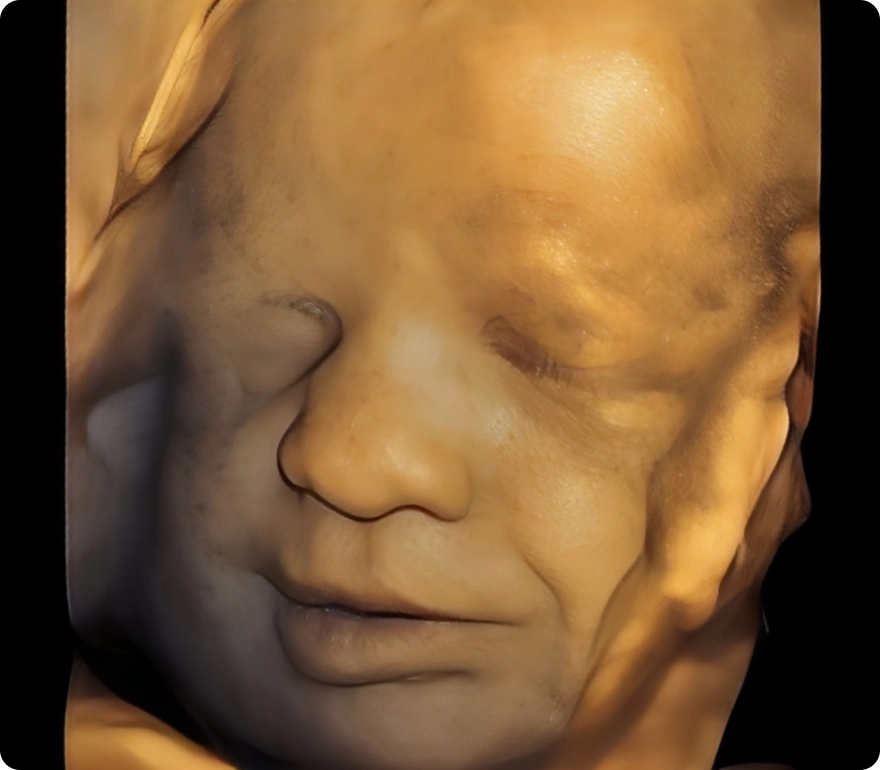

Our advanced HD ultrasounds offer breathtaking clarity and detail, allowing you to see your baby like never before. Every image and movement becomes a memory—one you can share and treasure for a lifetime.

HD

Advanced technology with stunning clarity, color, and detail—offering the most realistic, lifelike view of your baby before birth.